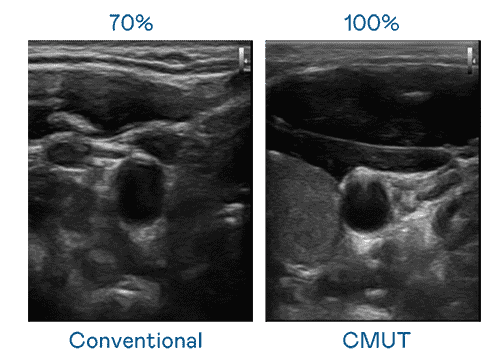

CMUT 技术是一种用电容式微机电元件来产生超音波讯号的技术。。。与传统 PZT 压电式技术相比,,CMUT 频宽增加 30%,,更宽频的超音波讯号让影像解析度大幅提升,,是实现高影像品质医疗超音波扫描、、促进精准医疗发展的关键技术。。。。

大频宽带来超清晰影像

超音波影像的解析度高低,,首先取决于探头能发出的讯号频宽。。糖果派对 CMUT 可提供高清晰的超音波讯号,,提供高频宽、、、、高灵敏度、、、影像纹理细节更高的超音波影像,,协助医护人员缩短影像判读时间及利用精准的医疗影像进行诊断。。